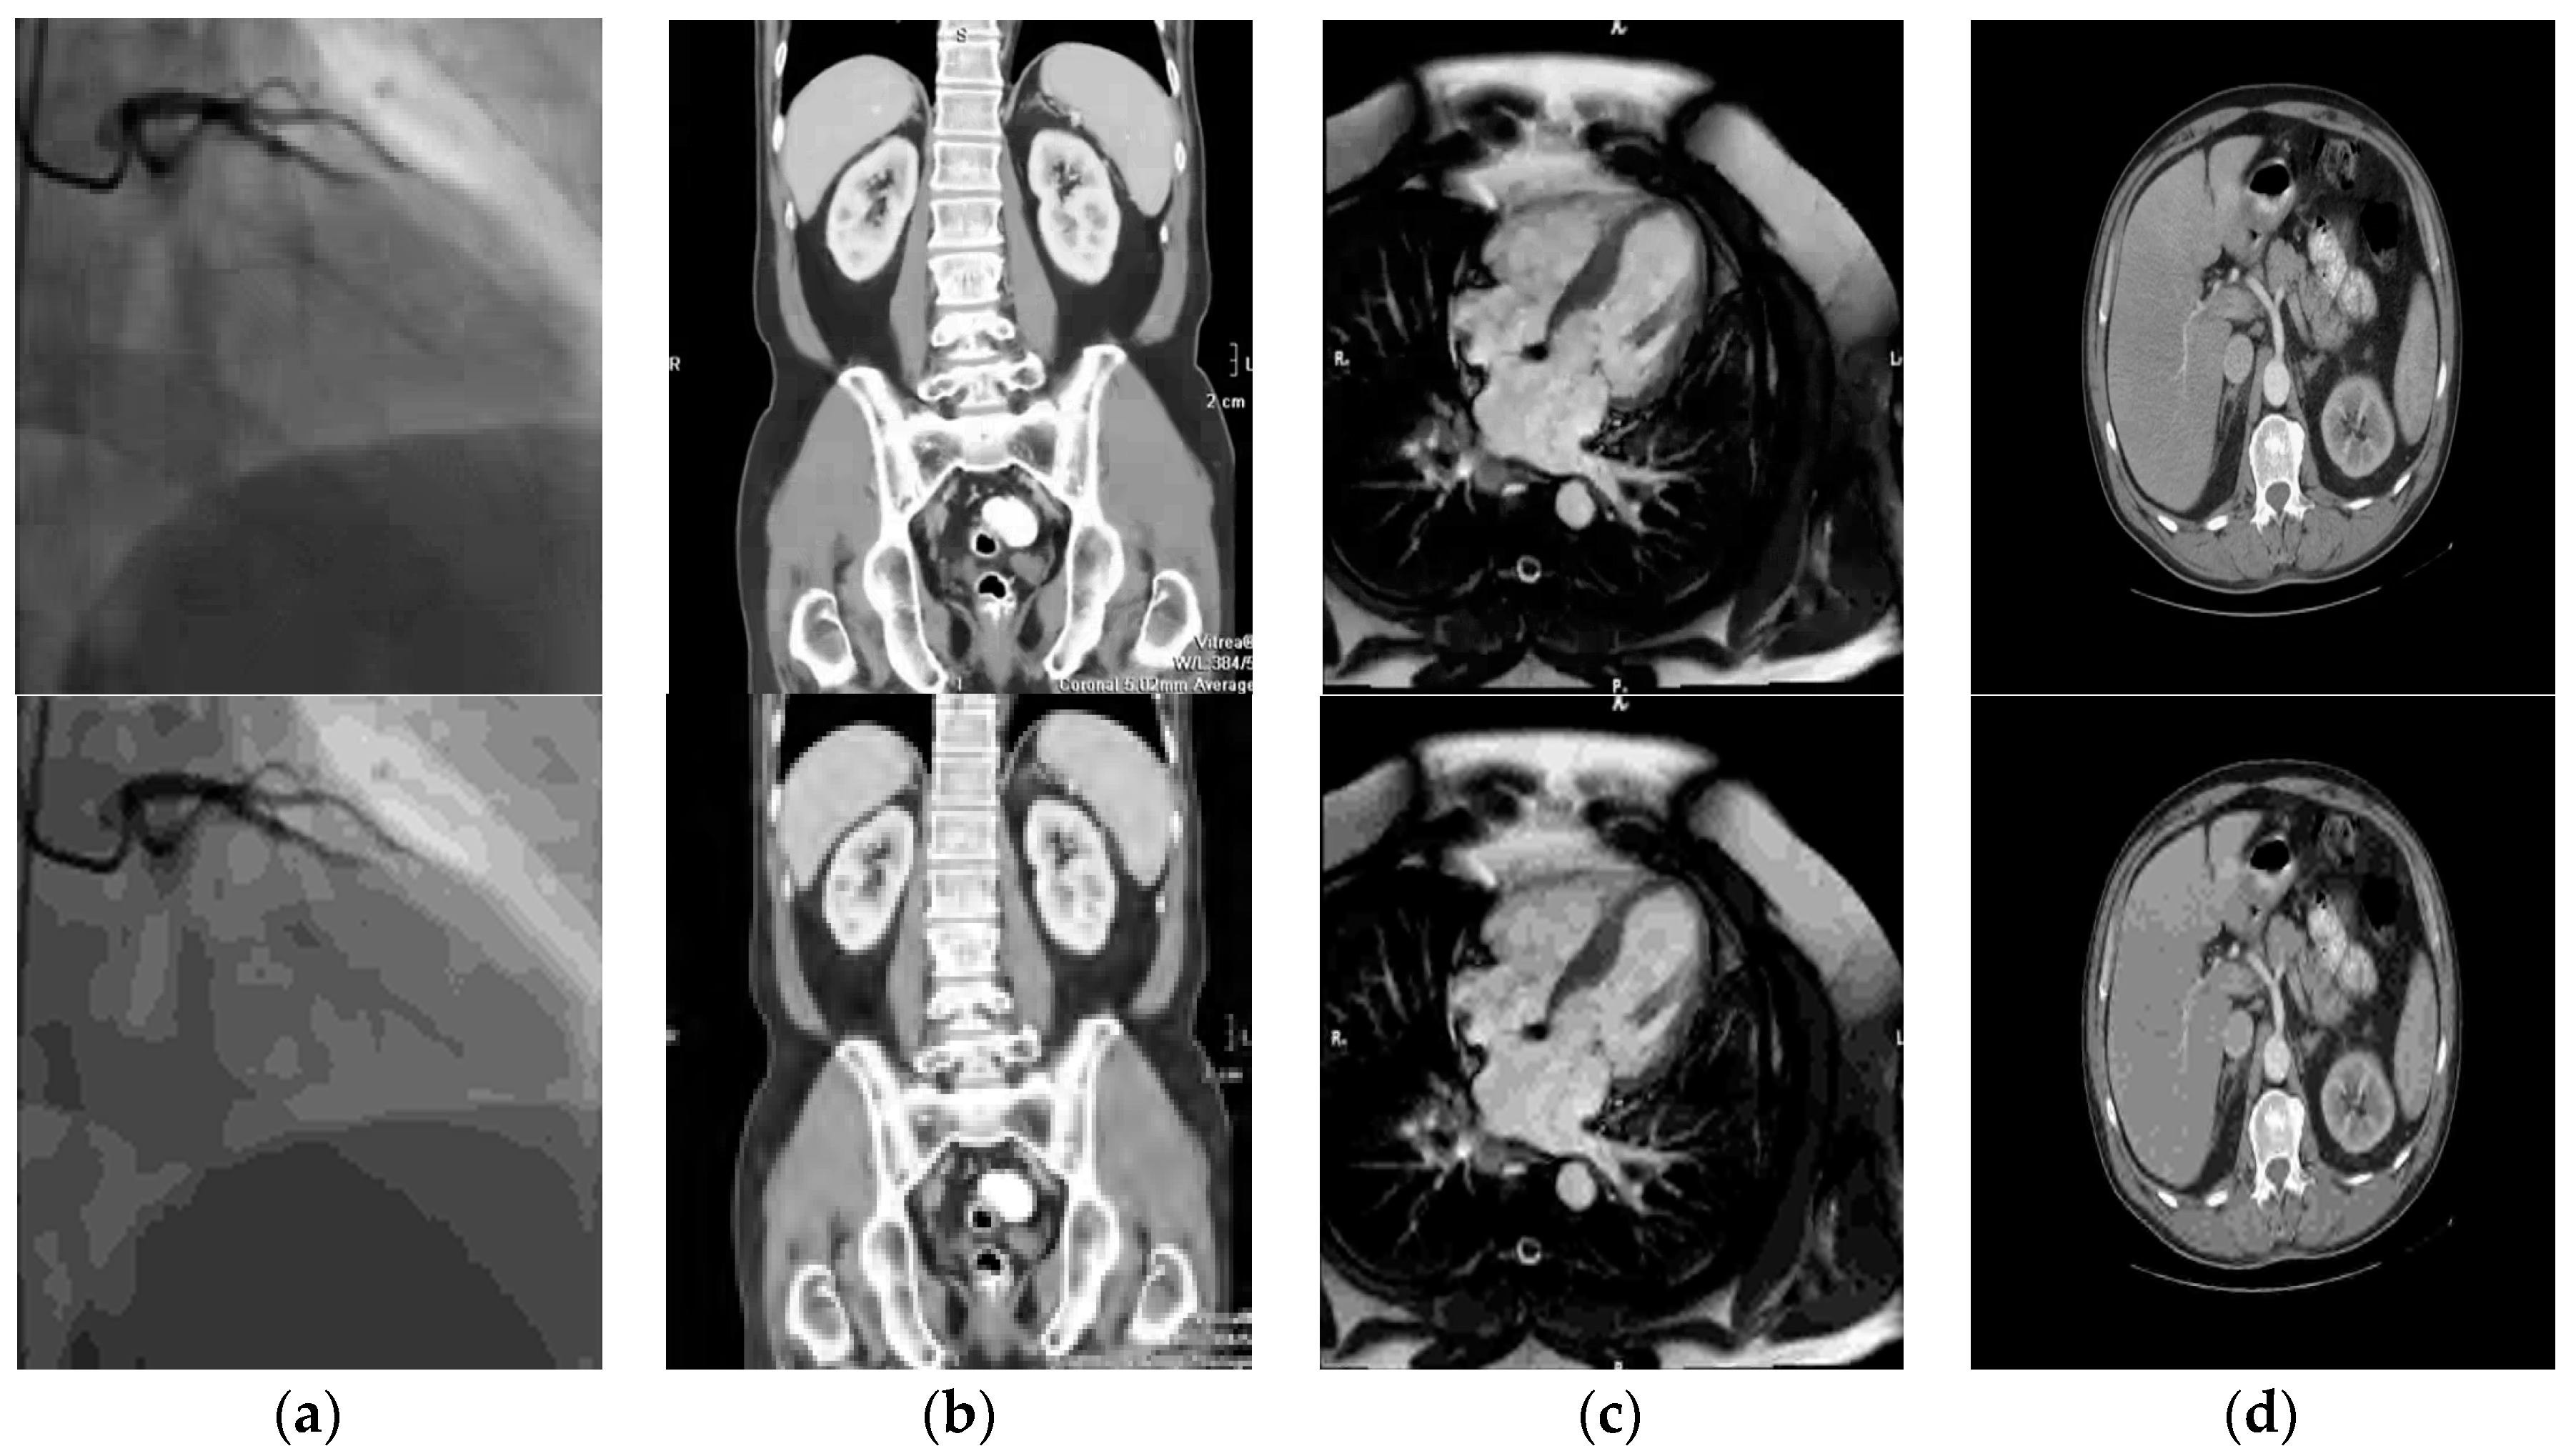

Figure 10 is an illustration of a sample of medical images from our large databases used for benchmarking (subjective quality assessment by visual inspection).

Figure 10.

Comparative subjective quality assessments medical video using bandelet (CDF9/7)-SPIHT (top row), and wavelet (CDF9/7)-SPIHT (Bottom row) at 0.5 Mbps. (a) Coronary angiography-X-ray; (b) abdomen/pelvis-computed tomography (CT); (c) heart-axial MRI; (d) bladder-MRI.

The images shown in Figure 10 are a simple illustration and their technical and medical characteristics are summarized in Table 1 (see also Figure 6). They represent: (a) Coronary angiography-X-ray; (b) abdomen/pelvis-computed tomography (CT); (c) heart-axial MRI; (d) bladder-MRI.

From these results, illustrated by some examples in Figure 8, Figure 9 and Figure 10, we can draw three conclusions:

- 1

- The performance of bandelet-SPIHT algorithm is superior to that of SPIHT (wavelet-based).

- 2

- Bandelet-SPIHT is able to capture complex geometric contents of images and surfaces and reduce drastically existing redundancy in video while classical SPIHT (based on discrete wavelet transform) is subject to artifacts.

- 3

- The bandelet-SPIHT algorithm gives better results in the case of CDF 9/7 wavelet filters than in the case of Le Gall 5/3.